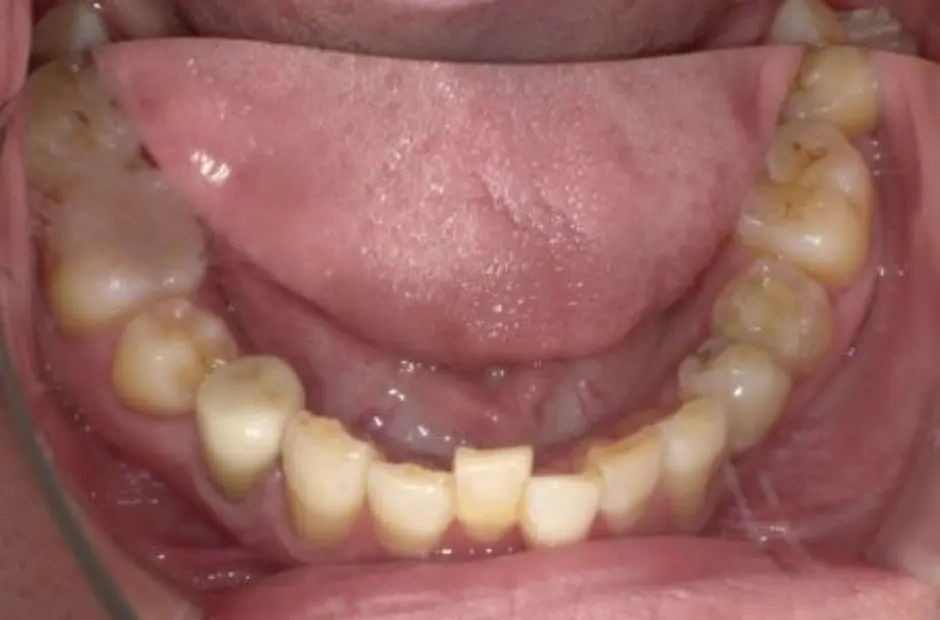

case.02

金属アレルギー治療の症例・治療前写真(銀歯7本)

金属アレルギー治療の症例・治療後写真(銀歯7本)

「 メタルフリーで、健康を手に! 」

当サロンのメタルフリー治療は、金属アレルギーの心配を排除し、健康な口内環境を実現します。高品質な非金属素材で安心と健康を手に入れましょう。

治療内容 古い銀歯を取り除き、レジンとセラミックを組み合わせて装着

治療期間/回数 2ヶ月/通院6回

施術当時の総額 220,000円(税込。検査・診断・手術関連処置費用などは含まない)。e-maxインレー:55,000円/1カ所

リスク・副作用 咬合による割れ